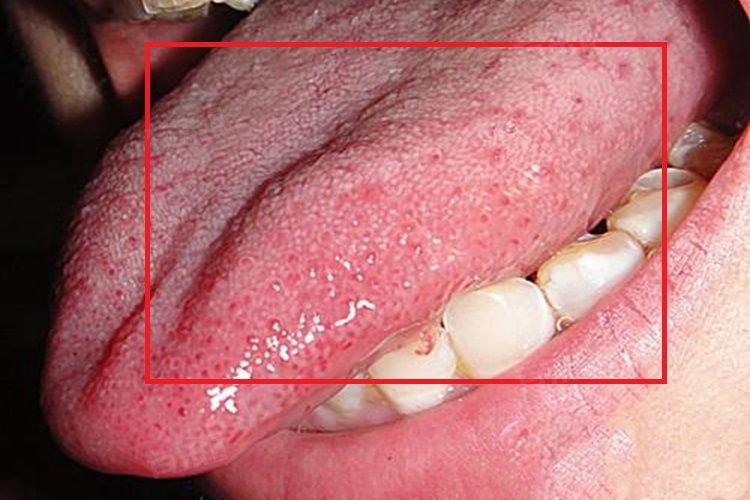

舌头上长了很多小颗粒可能由多种原因引起,常见的原因有丝状乳头、舌乳头炎、口腔念珠菌感染、疱疹性口炎等。

1、丝状乳头:是舌乳头中数量最多的,分布于舌背,呈白色丝绒状,具有一般感觉功能。如果观察到舌头上有很多细小、均匀分布的小颗粒,很可能就是丝状乳头,这是正常的生理结构,通常无需担心。

2、舌乳头炎:包括丝状乳头炎、菌状乳头炎等。局部刺激因素如锐利的牙尖、不良修复体、牙结石等,以及全身因素如营养不良、贫血、维生素缺乏等,都可能导致舌乳头炎,引起舌乳头充血、红肿,看起来像舌头上长了很多小颗粒,同时可能伴有疼痛、味觉异常等症状。

3、口腔念珠菌感染:由念珠菌属感染所引起的口腔黏膜疾病,好发于舌部等部位,可表现为舌背黏膜上的白色或灰白色斑块,周围黏膜可伴有充血、发红,有时也会感觉舌头上有小颗粒样改变,患者可能有口干、发黏、口腔黏膜烧灼感等症状。

4、疱疹性口炎:由单纯疱疹病毒引起,在口腔黏膜包括舌头上可出现成簇的小水疱,水疱破溃后形成溃疡,在水疱期可能感觉舌头上有很多小颗粒,常伴有发热、头痛、局部淋巴结肿大等症状。